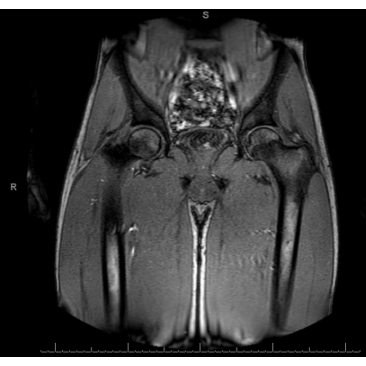

The athlete completed physical therapy with quick resolution of symptoms. He never required FFP. He played in his first game of the season 2 weeks after his formal diagnosis of Factor XI deficiency. One month later, a right lower extremity MR angiogram showed no structural vascular abnormality and a resolution of the hematoma with residual fascial thickening/inflammation.

Case Photo #3